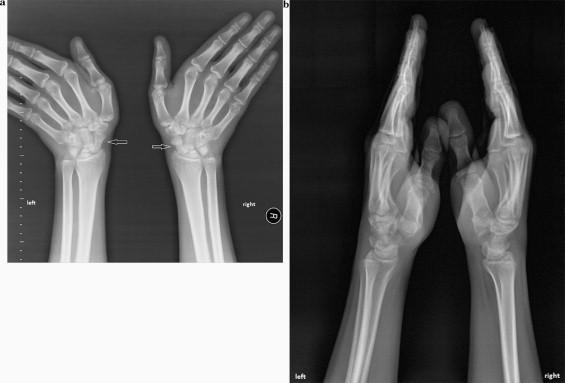

Bilateral scaphoid stress fractures are uncommon, and rarely presented with chronic wrist pain. Most fractures of the scaphoid heal with immobilization. Presentation of case The case presented here is of a bilateral stress fractures of the carpal scaphoid in a 19-year-old male.The patient had been playing as a goalkeeper and presented with a 4-year history of chronic pain in both wrists. We had a successful result in the treatment of these stress fractures with long- arm thumb plaster cast.Discussion Most fractures of the scaphoid in the immature skeleton heal with immobilization. Approximately 88-95% of acute scaphoid fractures are said to heal with conservative treatment using cast immobilisation. Non-surgical treatment is successful for scaphoid fractures in children and for those fractures which are non-displaced, stable, and where there is no damage to other bones or ligaments. In stable fractures, union is achieved within 8-12 weeks.Conclusion Bilateral stress fractures of the scaphoid can be considered for the wrist pain, especially for the patients that had repetitive minor wrist trauma, and in spite of developments in surgical techniques and materials used, treatment by plaster casting should still be considered initially for non-displaced, stable scaphoid stress fractures.

双侧舟骨应力性骨折并不常见,很少表现为慢性腕部疼痛。大多数舟骨骨折通过固定治疗可愈合。病例介绍 此处介绍的病例是一名19岁男性的双侧腕舟骨应力性骨折。该患者一直担任守门员,双腕部有4年慢性疼痛病史。我们采用长臂拇指石膏固定成功治疗了这些应力性骨折。讨论 未成熟骨骼中的大多数舟骨骨折通过固定可愈合。据说约88 - 95%的急性舟骨骨折采用石膏固定保守治疗可愈合。非手术治疗对于儿童舟骨骨折以及那些无移位、稳定且未损伤其他骨骼或韧带的骨折是成功的。在稳定骨折中,8 - 12周内可实现愈合。结论 对于腕部疼痛,尤其是有反复轻微腕部创伤的患者,应考虑双侧舟骨应力性骨折。尽管手术技术和所用材料有所发展,但对于无移位、稳定的舟骨应力性骨折,最初仍应考虑石膏固定治疗。